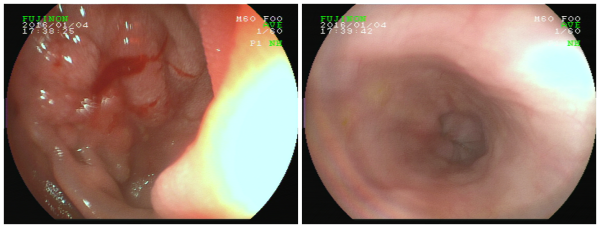

异物取出手术后

由于异物所在位置为十二指肠球降交界处,异物尖部已经插入小肠壁,若操作稍有不慎,异物尖部可能会划破肠壁及周围的脏器,引起肠穿孔或脏器大出血。在胃镜视野下,袁主任发现嵌在林先生患处的是一根包裹着食物残渣和胆汁的牙签!经过一个多小时细心谨慎的手术,一根约6.5cm的牙签被医生从林先生体内的十二指肠中取出,手术很顺利。术后,林先生便不再感觉腹痛,医生表示,再住院观察两天,林先生便可以出院了。